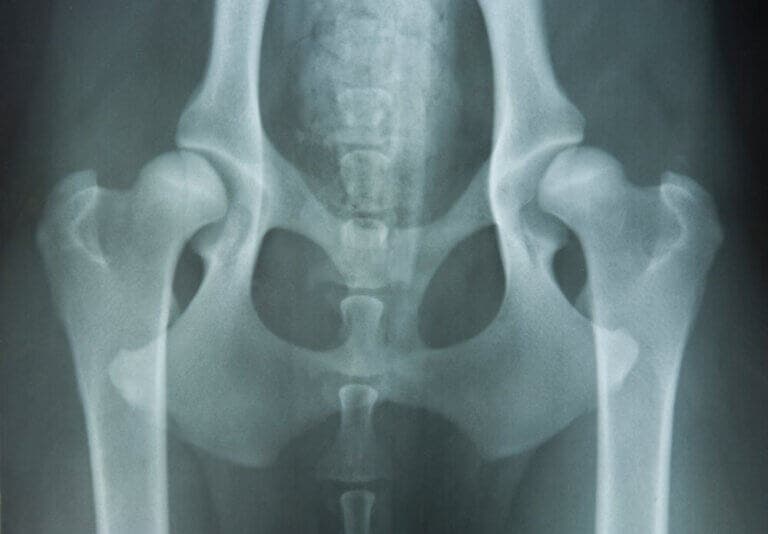

El estudio radiológico resulta fundamental para confirmar la afección ósea e intentar aproximarse a un diagnóstico preciso. Este proceso requiere de profesionales especializados.